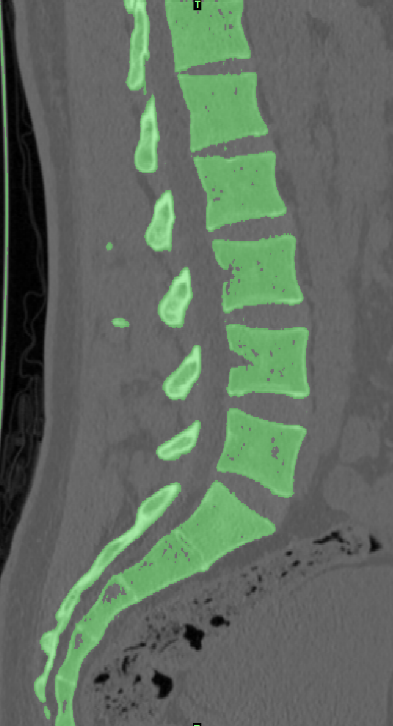

選取一名27歲青年男性志愿者在我院行腰椎螺旋CT掃描,掃描平面為:第十二胸椎椎體至尾椎末端,掃描厚度為0.625mm,得到二維斷層CT圖像489張,以DICOM格式進行儲存,導入計算機服務器。使用Mimics 19.0圖像生成和編輯處理軟件,直接讀取 DICOM格式的CT掃描數據進行三維重建,見圖 10。根據軟件中不同的灰度值來區分不同的組織,用 Mimics 軟件的閾值分割及區域增長功能畫出腰椎(L3-5),不同的錐體用不同的顏色區分,最后用圖像填充功能填補圖像中的空洞,接著進行不同部位的三維重建,得到僅包含骨性結構(L3-5)的模型。將Mimics 軟件得到的模型以STL格式模型文件導入Geomagic wrap2017軟件中,抹去模型釘狀物和多余特征,然后對模型進行優化光滑處理,將L3-5光滑處理后的每個錐體進行復制,再將光滑后的模型在精確曲面中進行網格劃分,并進行構建曲面片及修理曲面片,最后合成三維實體模型,見圖11。此時將復制的每個椎體模型外層向部件內部偏移2mm,內部充當松質骨,外部的則定義為皮質骨,椎弓根后部統一由皮質骨組成。隨后將模型以STEP格式文件導入Solidworks2020軟件中生成L3-5的實體模型零件,并在模型零件中構建椎間盤、髓核、上下終板和軟骨,完成的實體模型,此時的模型為單純的正常腰椎三維幾何模型,各結構并未賦予材料屬性與網格劃分,見圖12。將模型導入ANSYS軟件中,隨后對模型中皮質骨、松質骨、軟骨、終板、纖維環、髓核賦予相應的材料屬性賦值,盡可能地還原各組織材料的生理狀況,提高模型的可靠性。定義關節突關節面為 Frictional,摩擦系數設為0.1。在connections中建立spring?,模擬前縱韌帶、后縱韌帶、黃韌帶、棘間韌帶、棘后韌帶、橫突間韌帶及關節囊韌帶,各韌帶對應剛度賦值。建立完成后,對模型進行mesh操作構建網格,見圖13。